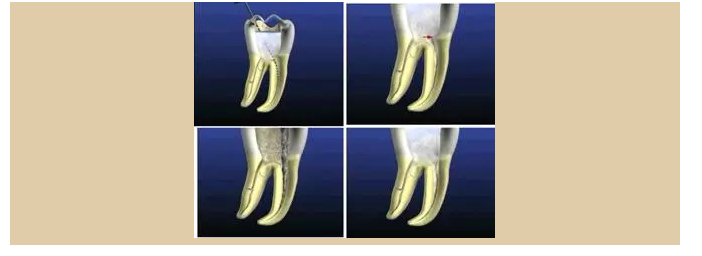

便宜形態(tài)是自切端或咬頜面朝向根尖的直線開擴(kuò)尖錐形態(tài),減少污染物推出根尖孔,方便沖洗、根管充填和側(cè)壁施壓。

保持形態(tài)是根尖狹窄部內(nèi) 1 — 2mm 的一段距離,由擴(kuò)大器回轉(zhuǎn)切割而不貼根管壁提拉切割制成,是擴(kuò)大器的原始形態(tài)(近似平行)。在測試主牙膠尖時給測試者有一個牽引抵抗 (tugback) 的感覺。

抵抗形態(tài)是根管預(yù)備的根尖形態(tài),它是由擴(kuò)大器或根管銼尖端 75 度角自然切割而成。其目的是防止根管充填材超出根尖孔,并且使根尖封閉更加嚴(yán)密。